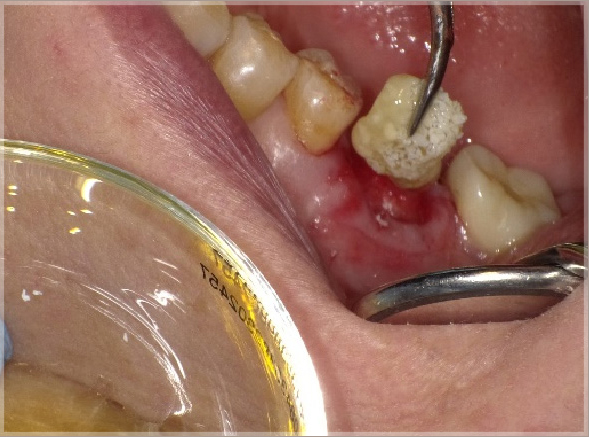

インプラントを埋入するときに重要なのは、しっかりとした土台があることと、インプラントが周りの骨ときちんと生着することです。

上の写真では、PRGFを使った場合インプラントの周りにしっかりと骨ができていることがわかります。しっかりとした骨をより早い期間で再生できれば、長期に渡るインプラント治療の期間が短くなるだけでなく、その後の経過にもよい影響が出ます。